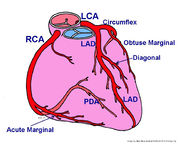

| 10:40, 18 May 2012 | Figure 3.jpg (file) |  |

691 KB | 1 | |